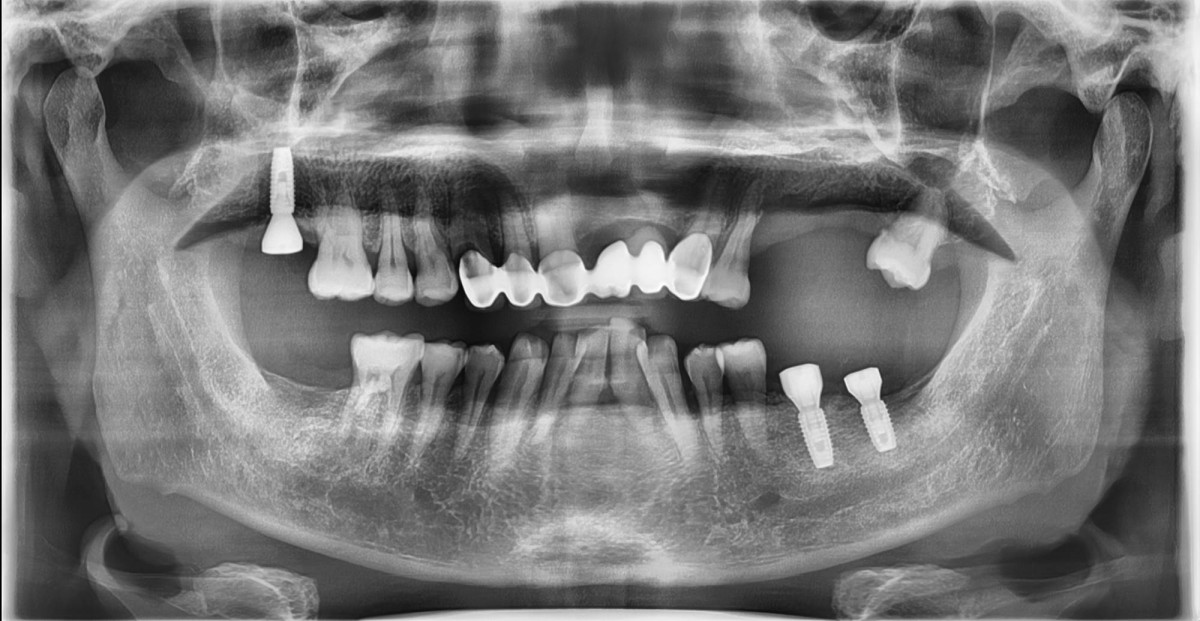

In the anterior maxilla, implant-supported fixed partial denture.

<GCpbc> A 58-year-old male is a patient undergoing implant installation in various parts. The old Br of the anterior maxilla has fallen

off and it is no longer possible to maintain it even temporarily, so a

treatment plan for the anterior teeth was made.